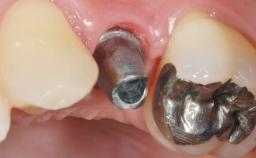

Early Placement of an Implant in a Maxillary Right Central Incisor Site

This 41-year-old female patient was referred to the clinic for the replacement of the right central incisor, since the tooth had developed a root fracture in the long axis that made extraction necessary. The healthy, non-smoking patient was first seen with the tooth still in place. A detailed Esthetic Risk Assessment was performed.The patient was worried about her dental esthetics and had high expectations for a successful treatment outcome from an esthetic point of view. The patient had a medium lip line that displayed parts of the gingiva in the anterior maxilla upon smile.